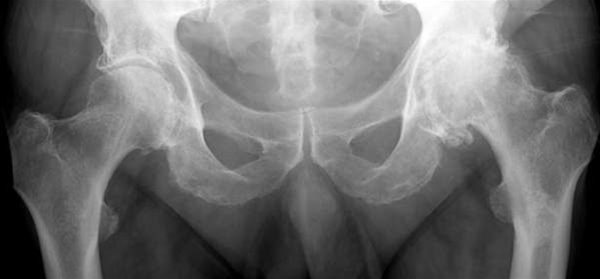

Coxartrose bilateralt

Let artrose i højre hofte med reduceret bruskhøjde og mindre knogleudbygninger omkring ledkanten af caput femoris (venstre side af billedet)

Udtalt artrose i venstre hofteled med næsten udslettet ledbrusk og ledspalte, knogleudbygninger (osteofytter) omkring leddet, subkondral sklerosering og cystiske opklaringer (højre side af billedet).